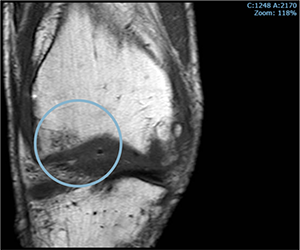

PRE-TREATMENT

NOVEMBER 2023

POST-TREATMENT

NOVEMBER 2024